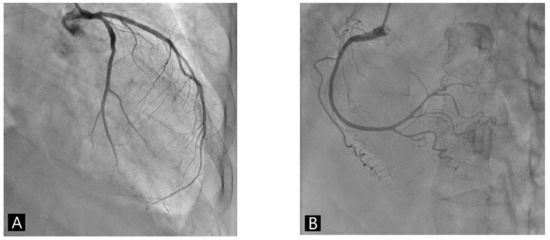

Cardiovascular events such as myocarditis following mRNA COVID-19 vaccination are increasing. We present a 67-year-old postmenopausal woman with Takotsubo Syndrome and Graves’ disease after mRNA COVID-19 vaccination. She developed chest pain and shortness of breath one week after vaccination. An electrocardiogram revealed ST [...] Read more.

Cardiovascular events such as myocarditis following mRNA COVID-19 vaccination are increasing. We present a 67-year-old postmenopausal woman with Takotsubo Syndrome and Graves’ disease after mRNA COVID-19 vaccination. She developed chest pain and shortness of breath one week after vaccination. An electrocardiogram revealed ST elevation in the precordial leads. Coronary angiography revealed the absence of obstructive coronary artery disease, and the left ventriculography showed a typical feature with apical ballooning. Laboratory workup showed the elevation of free T4 and thyrotropin receptor antibodies. It was presumed that Takotsubo Syndrome and Graves’ disease were probably related to the COVID-19 mRNA vaccination. The patient was treated with low-dose bisoprolol, diuretics, carbimazole, and steroid and discharged uneventfully. The mRNA COVID-19 vaccination is still safe and effective to defend against COVID-19 pandemic. However, clinicians should be aware of the possible cardiovascular adverse events other than myocarditis following vaccination. Full article